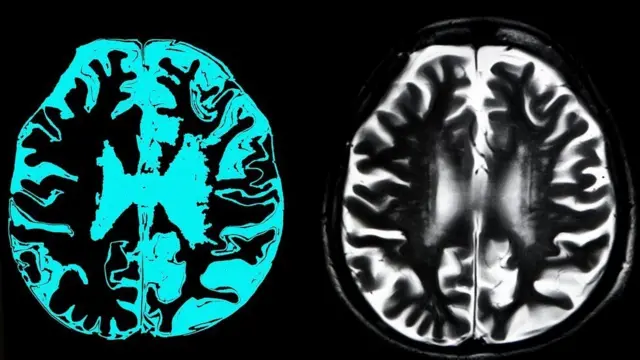

ኣብቲ ግዜ እቲ፡ ብዙሓት ተመራመርቲ ስነ ፍልጠት፡ እቲ መድሃኒት ኣብ ሓንጎል እቶም ኣልዛይመርስ ዘለዎም ዝርከብ ኣምይሎይድ ዝተባህለ ኣብ ሓንጎል ሰባት ጸገማት ዝፈጥር ፕሮቲን ዕላማ ዝገበረ'ኳ እንተኰነ ብዙሕ ከም ዘይጠቅም ገሊጾም እዮም።